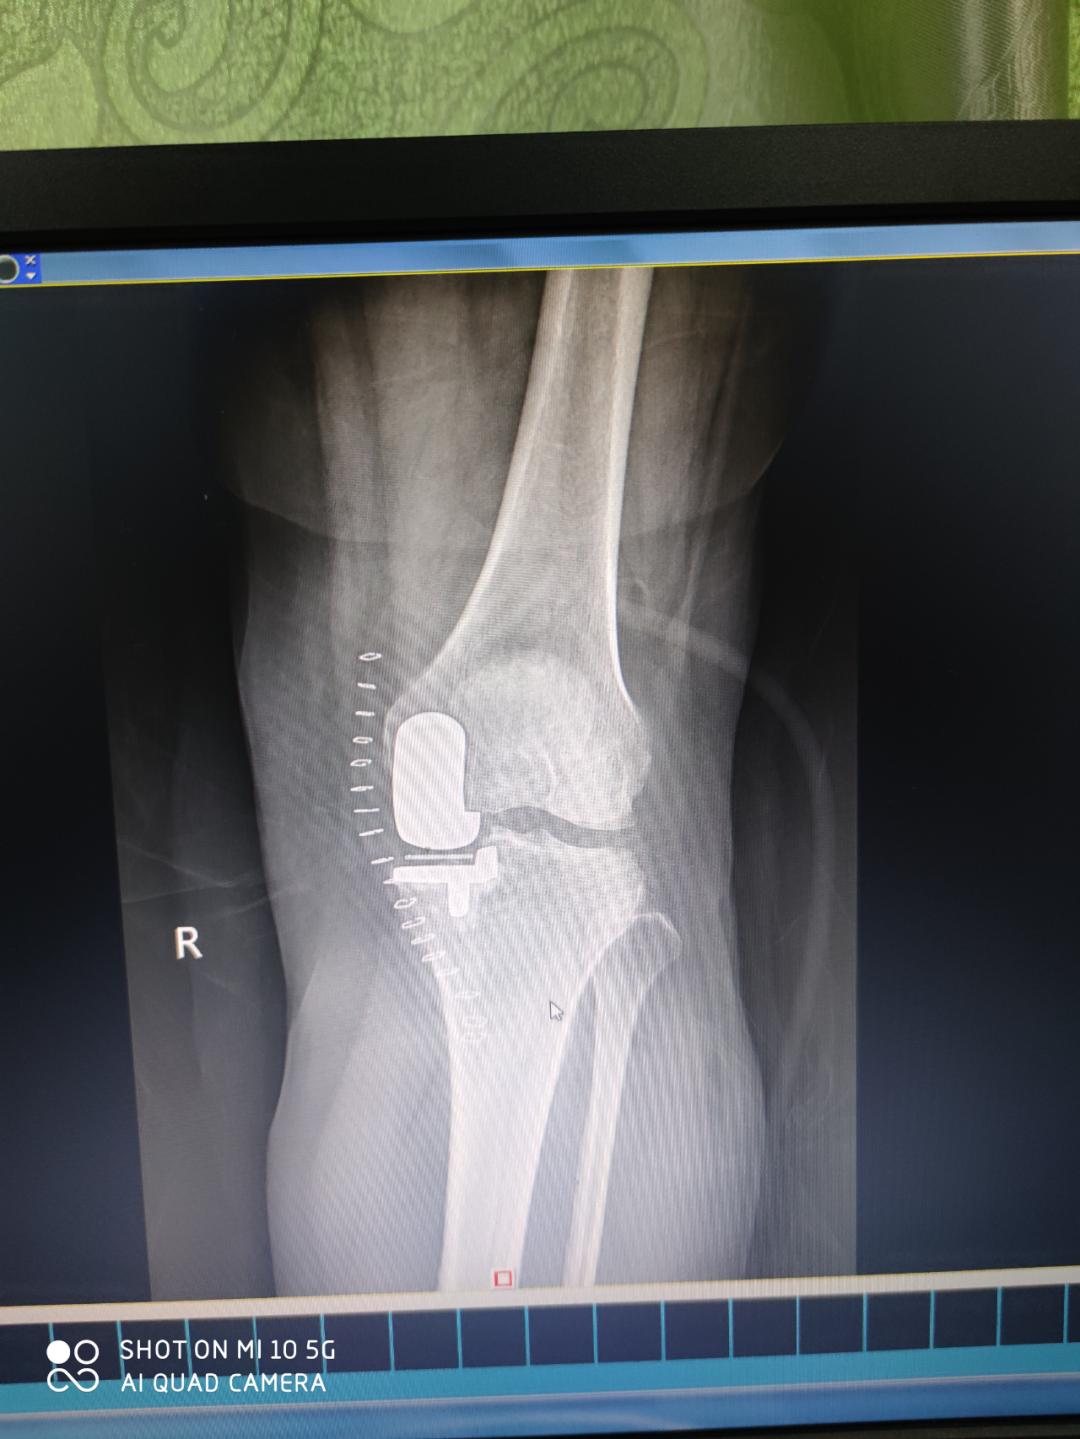

患者入院后,科室专家们为患者进行病情讨论,制定治疗方案,最终,一致认为该患者左股骨远端自发性骨坏死诊断明确,有明确手术的指征,结合患者目前的年龄、工作情况及其病情需要,可选择行左膝关节内侧单髁置换术(UKA)进行治疗,手术由农家隆、杨稀仁、陈俊、蒙华伦、陆吉利等专家共同完成。治疗效果非常显著,术后第二天患者就可以扶拐下床。

术后